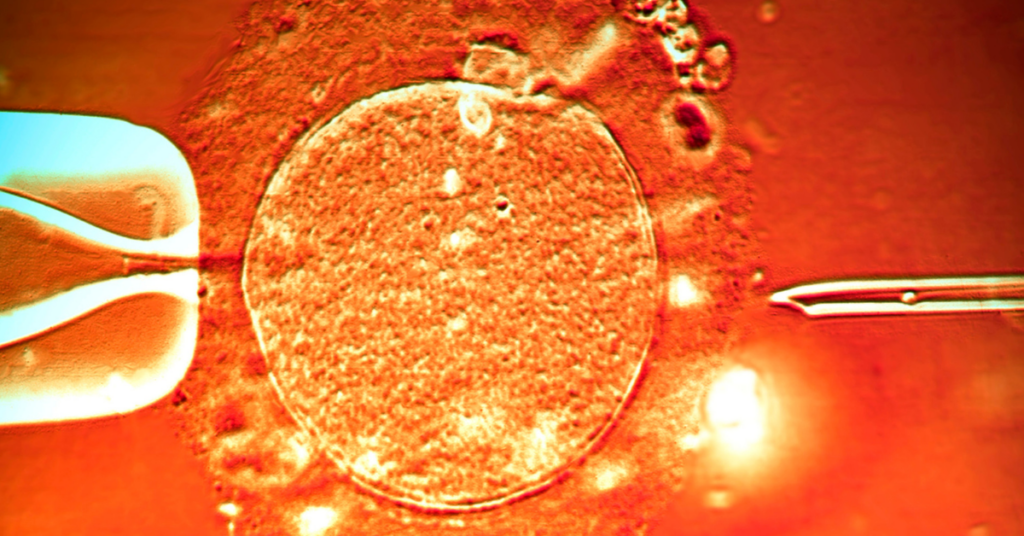

Cilj odloženog presecanja pupčane vrpce, kod zdravih porođaja u terminu, je da se omogući da deo krvi iz pupčanika uđe u novorođenče i poveća zapreminu krvi bebe i snabdevanje gvožđem.

Ovo ima brojne prednosti za bebu, ali smanjuje količinu krvi iz pupčanika koja se može uskladištiti za buduće zdravstvene potrebe bebe, bebine braće i sestara i bebine šire porodice.

Istraživanja su pokazala da u prvom minutu nakon zdravog porođaja beba dobija oko 80 odsto krvi koja će se vratiti iz pupčane vrpce, dok je u isto vreme količina krvi iz pupčane vrpce koja se može prikupiti za čuvanje u bankama krvi pupčanika prepolovljena.

Duže odlaganje pruža malu dodatnu korist za bebu, ali potpuno sprečava nakupljanje krvi iz pupčane vrpce. Medicinska udruženja akušera i ginekologa ne preporučuju odlaganje stezanja pupčane vrpce duže od jednog minuta.

Ako imate starije dete kome je potrebna krv iz pupčanika za terapiju, važno je da dobijete veliku količinu krvi iz pupčanika. Neke situacije u kojima se to može desiti su stariji brat ili sestra sa talasemijom ili stariji brat i sestra sa cerebralnom paralizom.

U ovom slučaju, roditelji treba da budu sigurni da će na porođaju biti prisutan neko ko razume važnost uzimanja krvi iz pupčanika i ko poseduje neophodnu obuku za flebotomiju. Taj neko treba pravilno da izvrši prikupljanje.